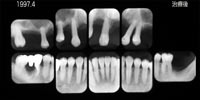

■症例 5.部分入れ歯の安定をよくするために用いたインプラントです。 私が最も得意とするインプラントの使い方です。「取り外しの義歯自体は受入れられるが、義歯の安定が悪いので何とかしたい」という場合に、最小限のインプラントを用いて義歯の支台とする方法です。固定性には及びませんが、手術侵襲や費用もはるかに小さくすることができます。1997年からこれらの使い方に取り組み、現在15年以上の経過と実績があります。